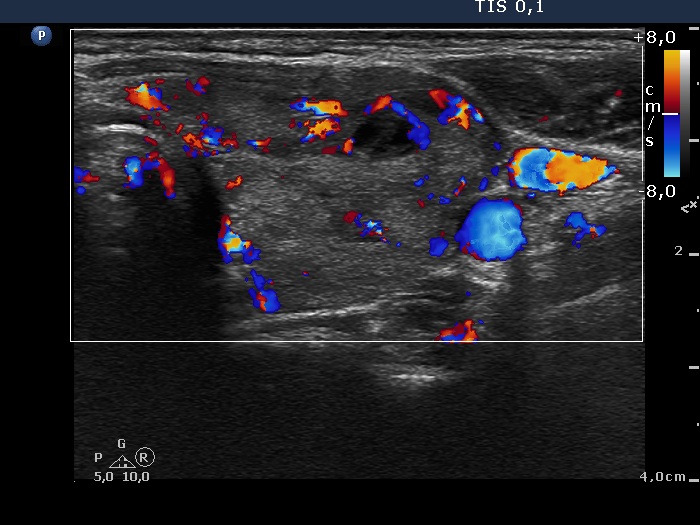

Case 1764

Follow-up examination 8 months after the previous visit (ultrasonographic picture 6)

Patient in hyperthyroid state without therapy

Left lobe, longitudinal scan, color Doppler mode. The vascularization of this lobe has also increased.